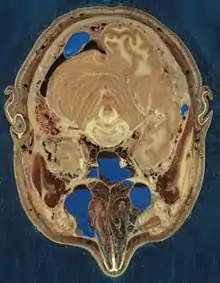

يتألف رأس الإنسان من قسم لحمي خارجي يحيط بالجمجمة العظمية، حيث يتوضع الدماغ، يستند الرأس على الرقبة، التي تؤمن له الدعم العظمي والقدرة على الحركة عن طريق سبع فقرات رقبية.

يمثل الوجه القسم الأمامي من الرأس، ويحوي الأعضاء الحسية مثل العينين والأنف والفم، يؤمِّن الخدان (الوجنتان) على جانبي الفم حدوداً لحمية لتجويف الفم. تتوضع الأذنان على جانبي الرأس